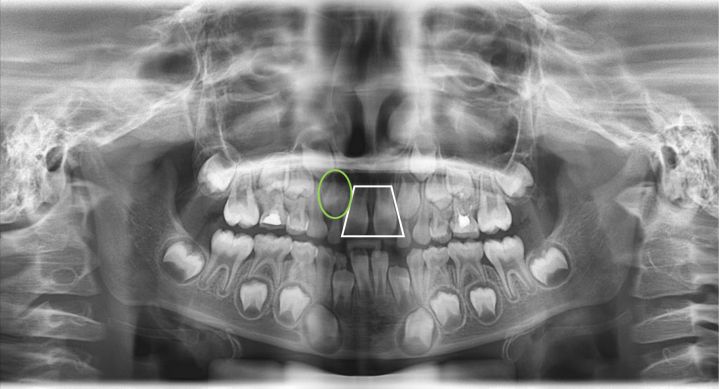

从上图可以看到,中间上牙中有较大的缝隙,当孩子在长牙阶段,上牙前部牙总是第一个长出来的,但是他旁边的牙齿也要萌出(绿色圈中),需要发育空间,就无法避免的会挤压到中间牙齿的牙根,牙根就被挤到中间,长出来那一部分自然就被挤到两边,就出现了大缝隙。